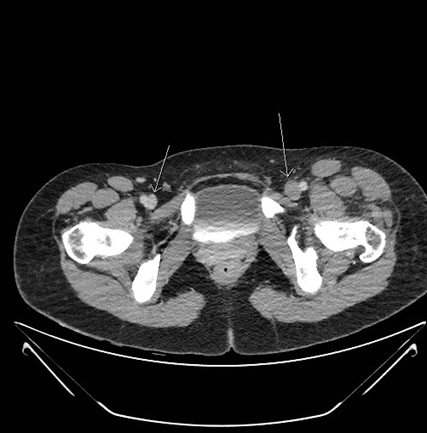

Venografía axial por CT donde se muestra un trombo agudo que va del filtro de VCI  hasta la vena ilíaca interna y externa derecha y la vena ilíaca común izquierda.

Venografía coronaria por CT donde se muestra un trombo agudo que va del filtro de VCI hasta la vena ilíaca interna y externa derecha y la vena ilíaca común izquierda.